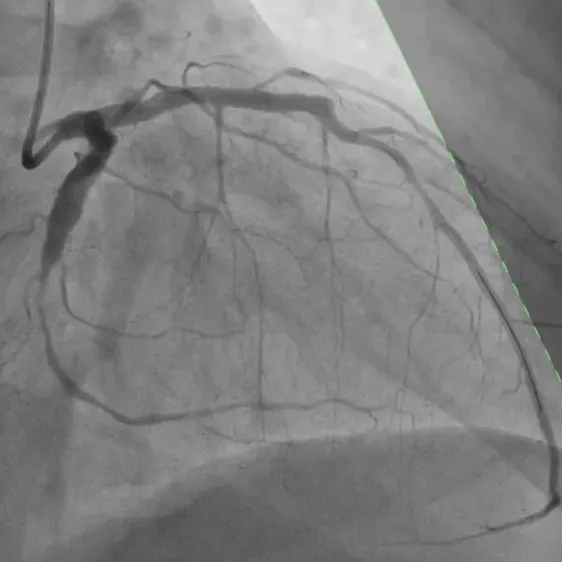

首例患者为一名患有冠心病的52岁男性,经术前冠脉造影检查显示左冠前降支和回旋支均有80%以上狭窄病变,需进行支架植入治疗,在与患者充分沟通并签署知情同意书后,手术顺利实施。

基线造影—左冠前降支

基线造影—左冠回旋支